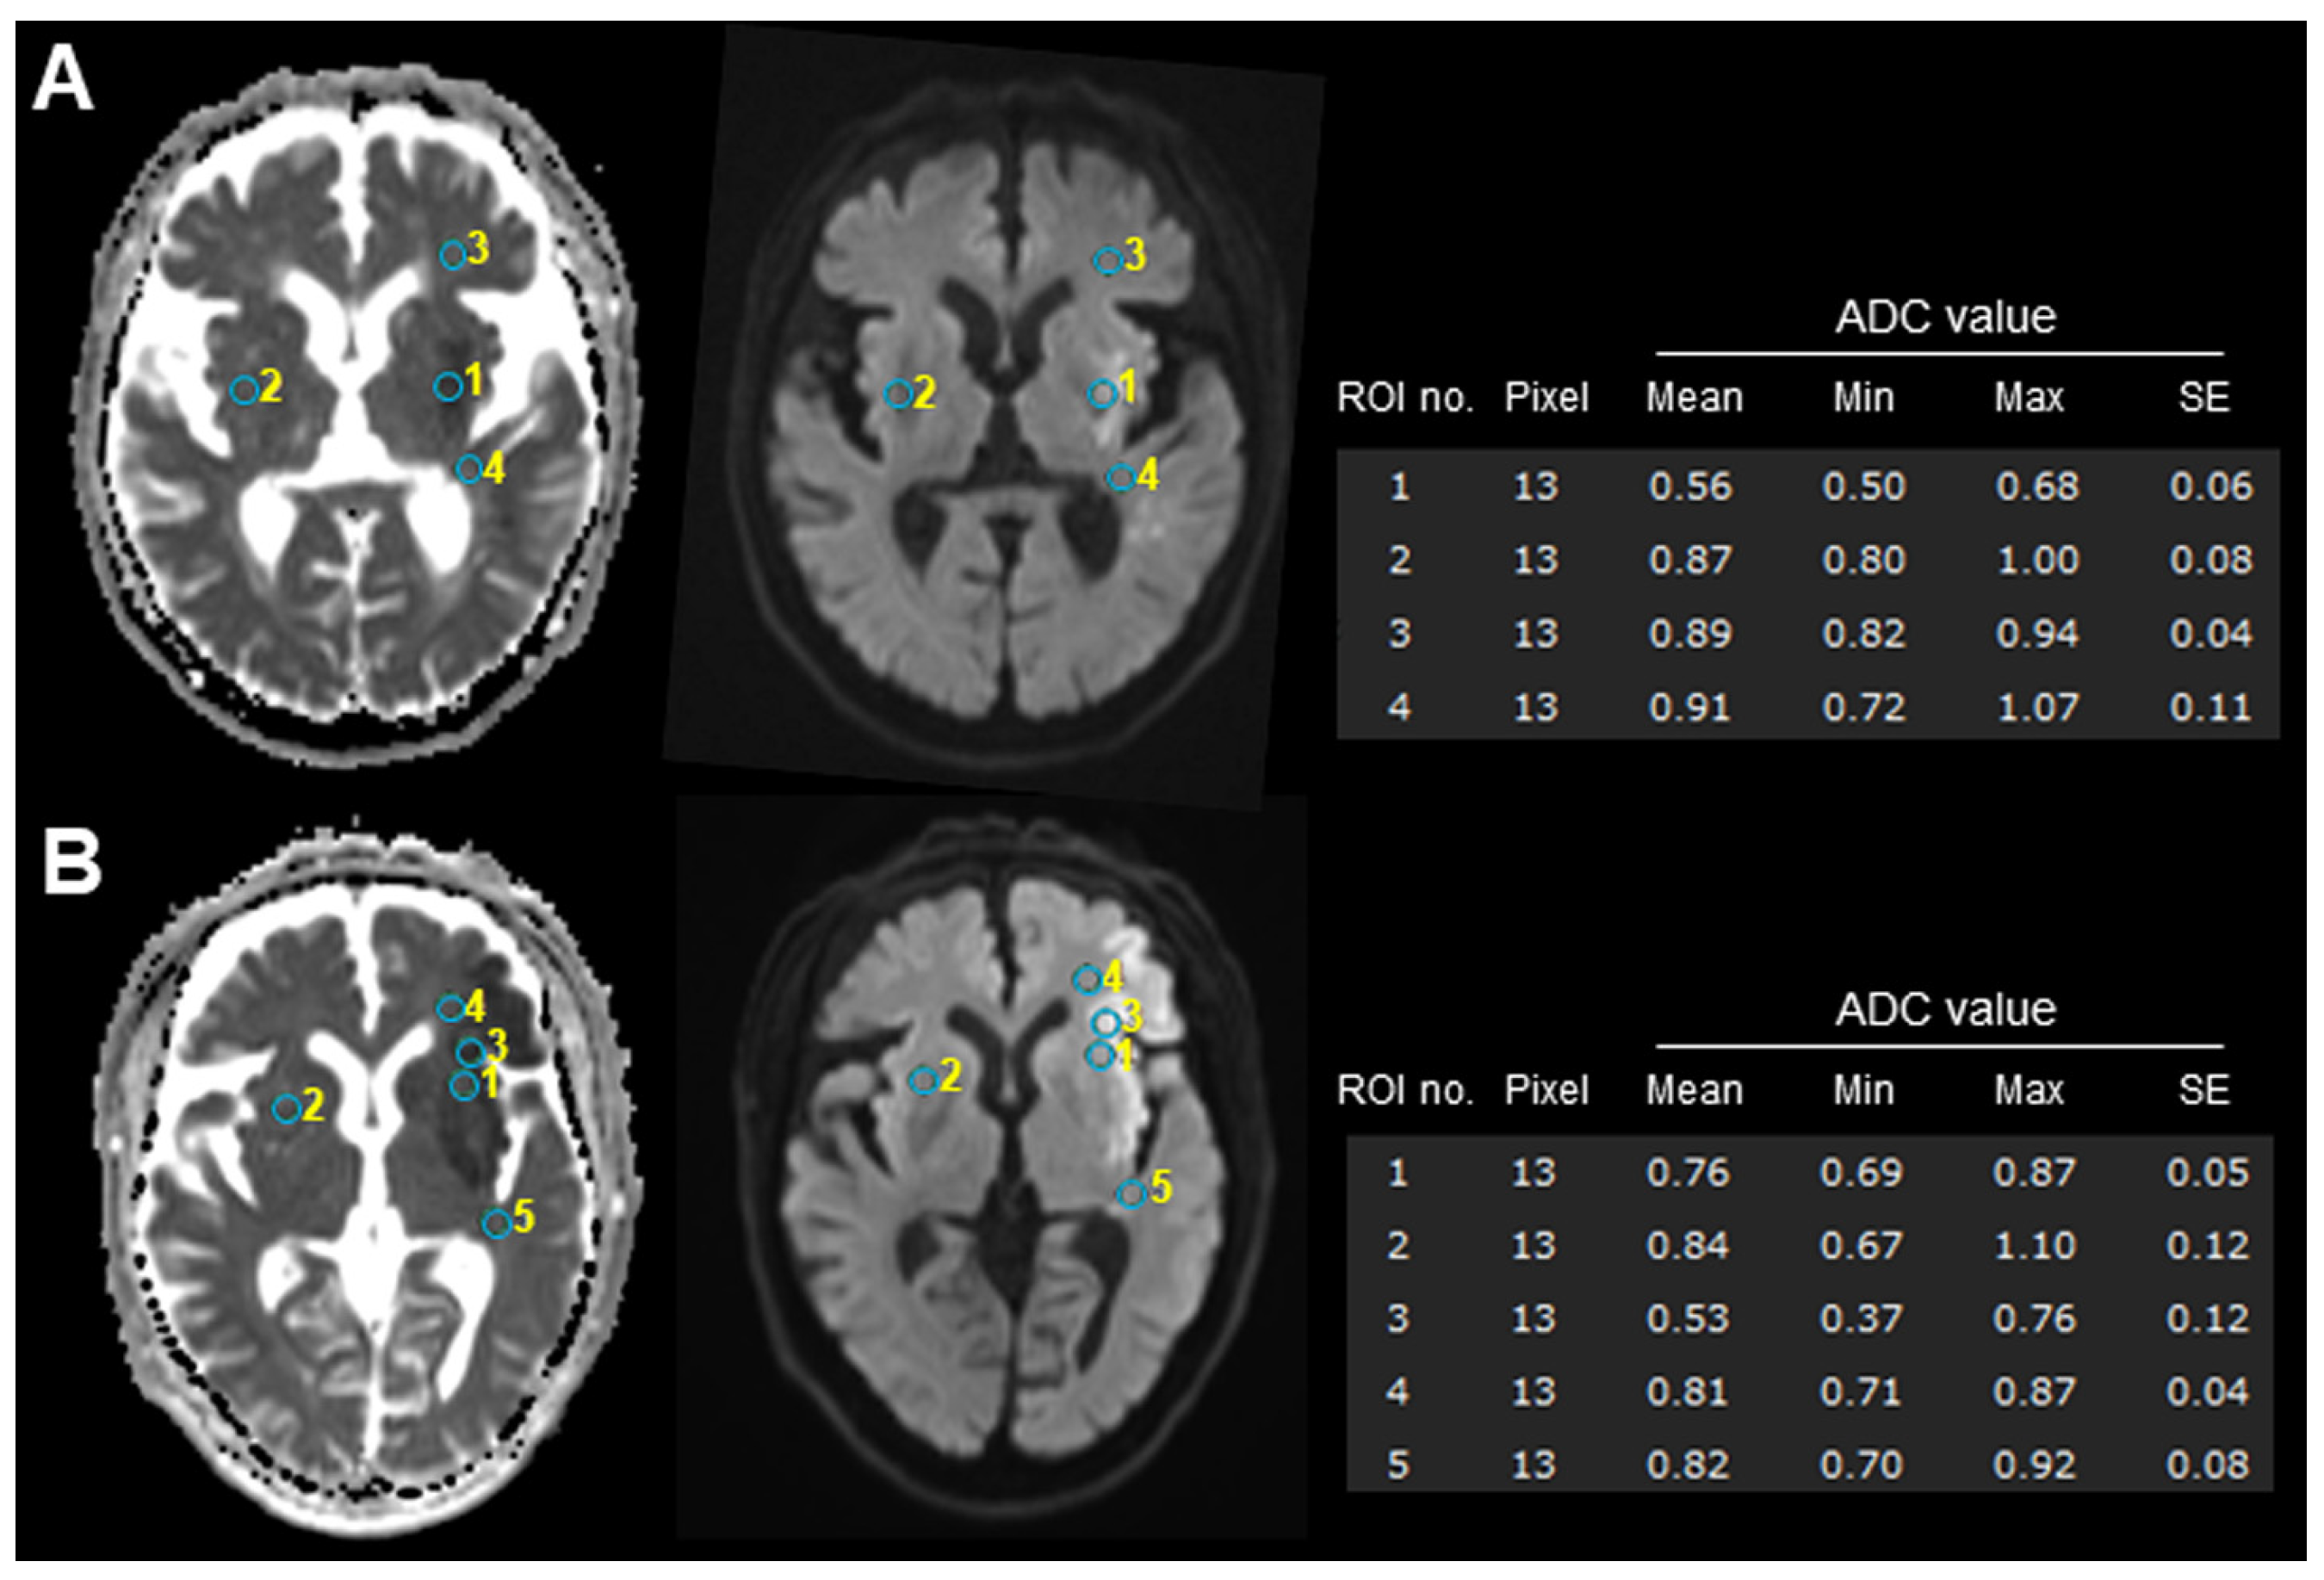

| ADC value, mean (SD) | 0.59 (0.11) | 0.52 (0.08) | 0.62 (0.10) | 0.006 * |